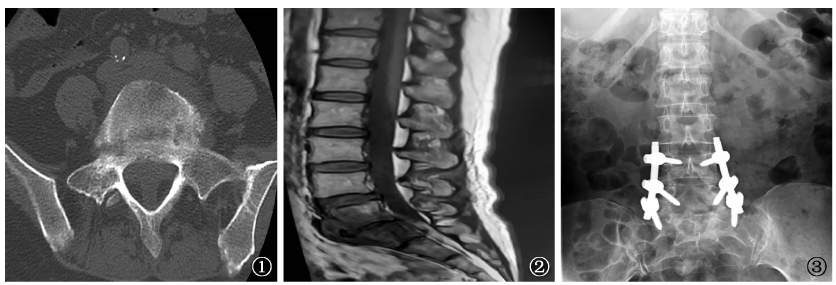

图1~3

病例1,女性,54岁。

图1

为2021年4月8日患者于陕西省结核病防治院拍摄的腰椎CT图像,显示骶1椎体边缘毛糙,局部见破坏征象,周围见软组织肿胀。

图2

为2021年4月9日外院腰椎MRI,显示腰5~骶1椎间隙狭窄,可见斑片状长T

1

、短T

2

信号影,压脂序列呈高信号,增强扫描明显强化,T

加权成像显示部分椎间盘信号降低,腰5~骶1椎间盘组织向椎体后方突出,硬膜囊受压,椎管狭窄,黄韧带无明显增厚,脊髓圆锥及终丝和马尾形态信号无异常改变。

图3

为2021年4月16日患者于我院行腰5~骶1后路病灶清除、椎管减压及钉棒内固定术